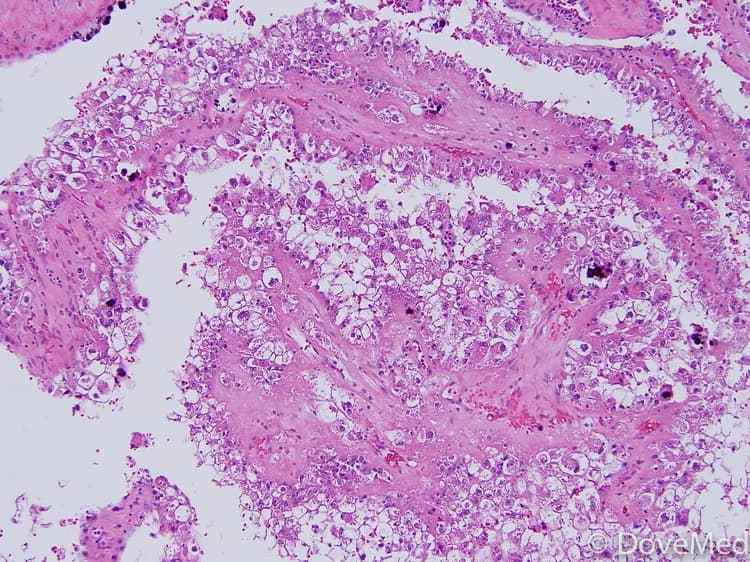

Test your knowledge on the medical condition Papillary Renal Cell Carcinoma and learn more about its cause, symptoms, diagnosis, complications, treatment, prevention, and prognosis.